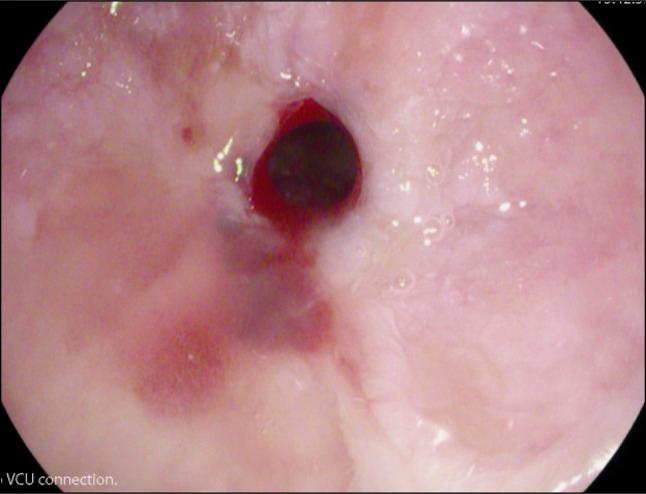

Complete esophageal obstruction (CEO) is a rare phenomenon usually observed after receiving head and neck radiation. Zollinger-Ellison syndrome (ZES) is typically associated with minimal esophageal morbidity because of advancements in antisecretory medications. There are currently no documented reports of CEO in patients with ZES. Although surgeries are available for the treatment of CEO, there is no established method for endoscopic lumen restoration, given its rarity. This case documents potential sequala of modern-day patients with ZES.

完全性食管梗阻(CEO)是一种罕见现象,通常在接受头颈部放疗后出现。由于抗分泌药物的进展,卓艾综合征(ZES)通常与最小的食管发病率相关。目前尚无ZES患者发生CEO的文献报道。尽管有手术可用于治疗CEO,但鉴于其罕见性,尚无成熟的内镜管腔恢复方法。本病例记录了现代ZES患者的潜在后遗症。